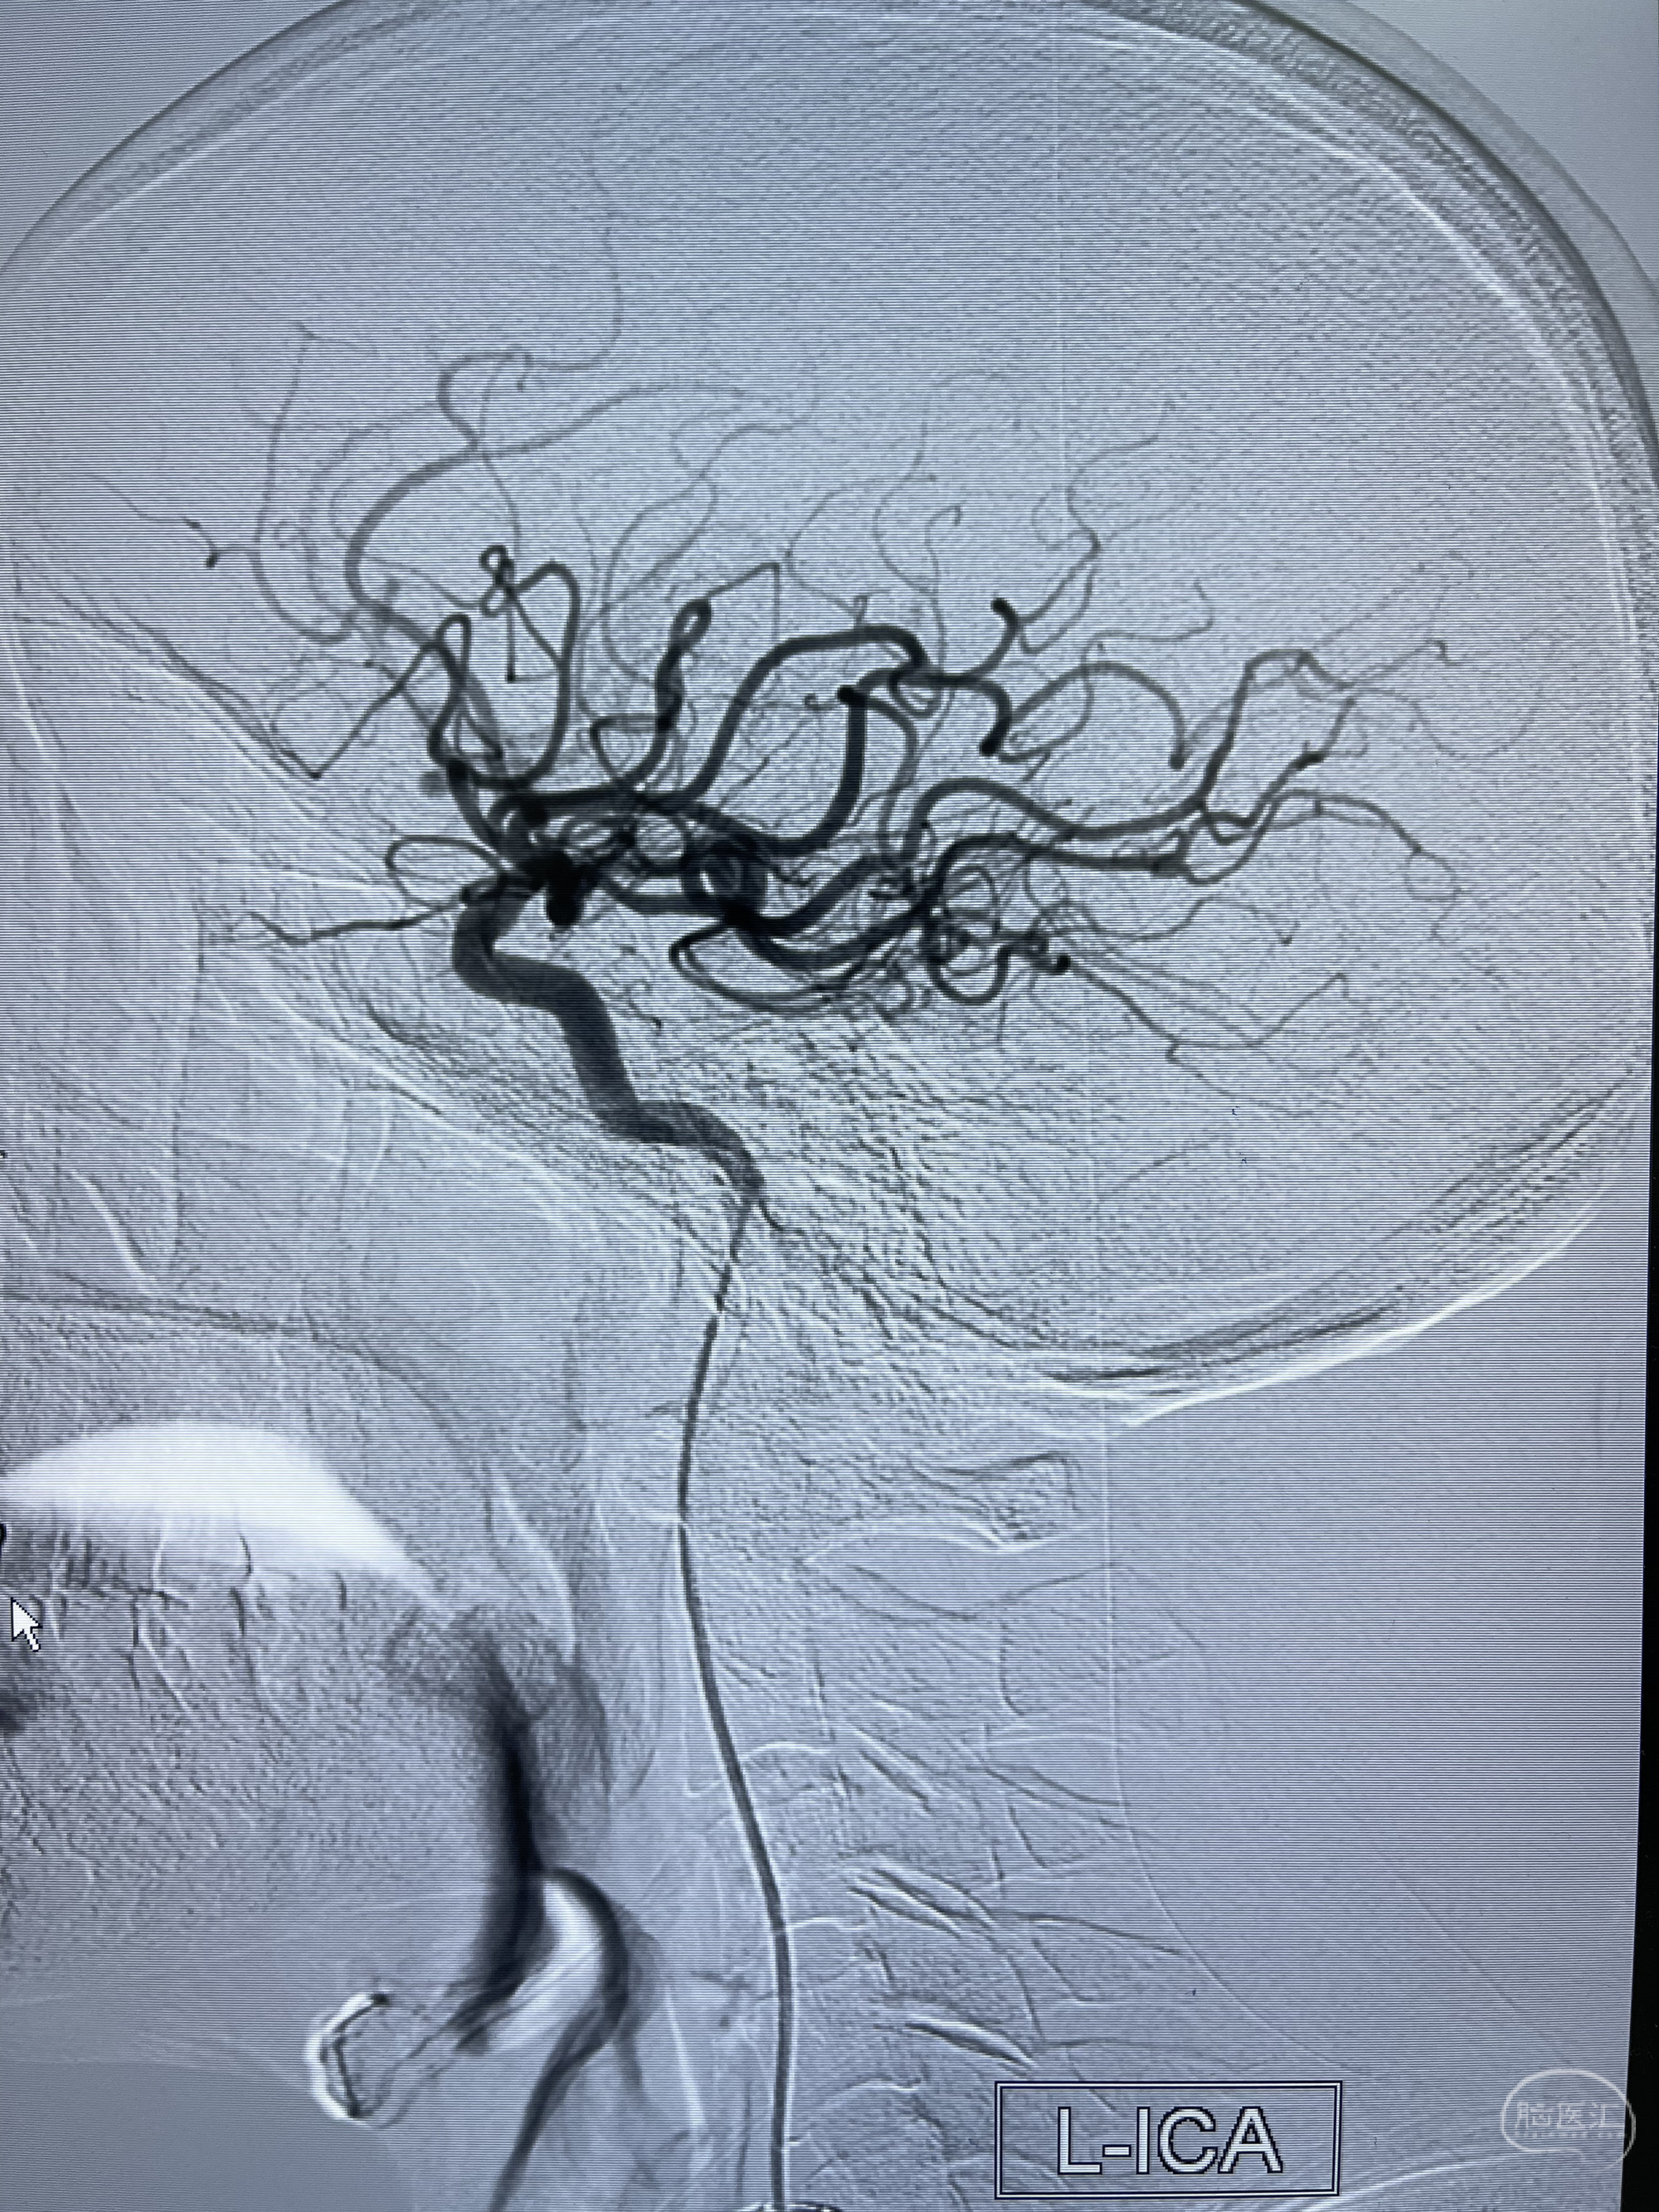

2.右侧颈内动脉由后循环经右侧后交通动脉前向代偿显示

3.右侧颈内动脉眼动脉段近后交通动脉处重度狭窄伴前壁不规则动脉瘤

2.狭窄远端颈内动脉由左侧颈内动脉经左侧后交通动脉—基底动脉顶—右侧后交通—右侧颈内动脉—右侧大脑中动脉途径代偿

左侧颈内动脉经左侧后交通动脉—基底动脉顶—右侧后交通—右侧颈内动脉—右侧大脑中动脉途径代偿

左侧颈外动脉经脑膜支吻合至左侧椎动脉—左侧锁骨下动脉—左侧上肢